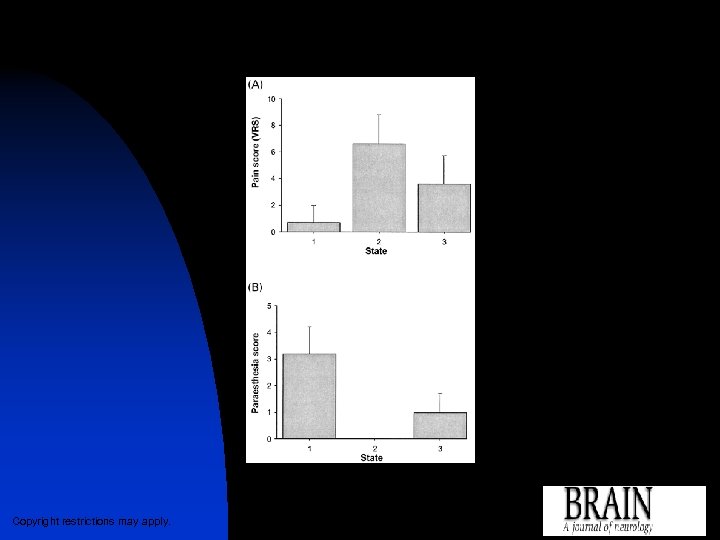

Graphs showing (A) mean pain scores and (B) mean scores of stimulator-induced paraesthesia by scanning states Matharu, M. S. et al. Brain 2004 127: 220 -230; doi: 10. 1093/brain/awh 022 Copyright restrictions may apply.